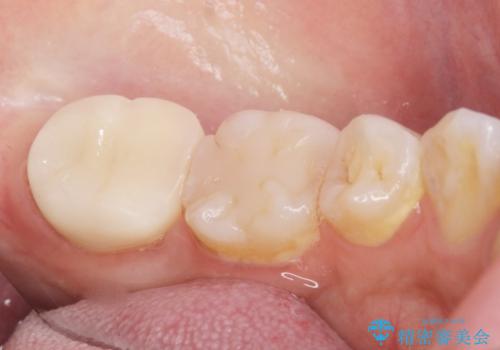

- 奥歯が黒くなっていることを気にされ来院された患者様です。

精査したところ、左下の奥歯にう蝕を認めました。

患者様のご希望により、う蝕を丁寧に除去したのちセラミッククラウンによる補綴治療を行いました。

セラミッククラウンの自然な仕上がりと咬み心地にご満足頂けました。

クラウンの種類:オールセラミッククラウン スタンダード